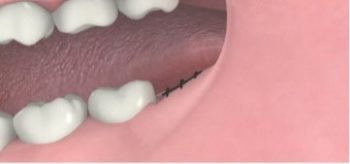

6. การเย็บแผลทำเพื่อลดการเกิดเลือดออกและให้แผลปิดอยู่กับที่ เพื่อการหายของแผลจะได้เกิดขึ้นรวดเร็ว